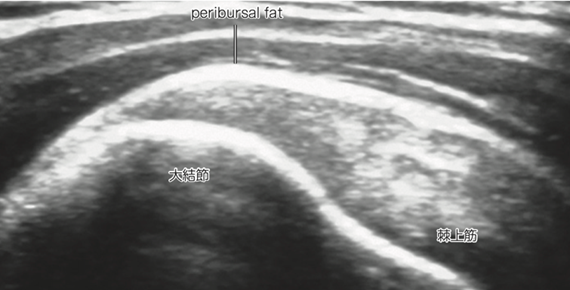

【特集】超音波(エコー)で見る、あなたの身体の中 -診断から最新治療まで-

近年、整形外科領域において超音波(エコー)検査は、腱板断裂の診断と「治療」において非常に重要な役割を担っています。

リアルタイム観察

エコーは、肩を動かしながら腱板の状態をリアルタイムで観察できるため、動的な病態評価が可能です。これにより、腱板の断裂部位や断裂の程度、周囲組織との関係性をより正確に把握できます。

エコー検査では、腱板の連続性の途絶や、腱の肥厚・菲薄化、炎症の有無などを確認します。これにより、腱板断裂の診断だけでなく、腱板炎や石灰性腱炎など、他の肩の疾患との鑑別も行います。

出典:西頭知宏, 笹沼秀幸, 飯島裕生, & 竹下克志. (2023). 関節の超音波所見. 臨床画像, 39(1), 18-25.